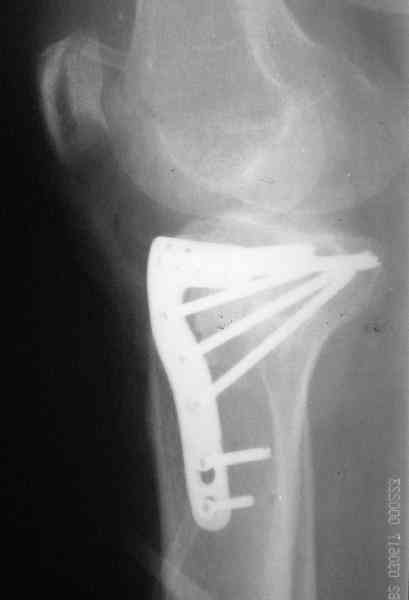

Наш план; доступ как подсказал Michael, по возможности репозиция, костная аутопластика дефекта метафиза, винты и спицы, АВФ и умеренная дистракция с шарнирными стержнями, и ранная пассивная разработка. Операцию планируем на следуюшей недели.

Уважаемый Абдурашид. Если нет противопоказаний , то из оперативных способов, я бы рекомендовал следующие: Полное замещение наружного мыщелка аллотрансплантатом либо открытая репозиция с элевацией и замещение дефекта ауто или аллокостью. В Ваших условиях , я бы рекомендовал второй способ. Во-время элевации необходимо разъединить фрагменты со стороны сустава ( надсечь скальпелем по линиям перелома, а затем тонким остеотомом их разъединить. При помощи долота произвести неполную остеотомию ( захватите не менее 1,5 - 2 см губчатой кости и поднять фрагменты, визуально отрепонировать и фиксировать 2-3 спицами. Дефект заместить костным ауто или аллатрансплантатом. Окончательная стабилизация пластиной ( лучше с угловой стабильностью, либо АВФ - позволит спокойно устранить угловую деформацию.

Через 3 месяца после перелома все еще можно выделить отломки, очистить от костной мозоли и и восстановить анатомию суставной поверхности. Фиксировать компрессионными шурупами. Важно помнить, что наружный мыщелок должен быть на 4-5 мм выше внутреннего. Передняя крестообразная связка обычно остается с частью кости и важно фиксировать ее проволокой по Ли. После восстановления суставной поверхности весь комплекс суставной поверхности нужно фиксировать к диафизу, можно использовать пластинку с фиксированными шурупами с наружной поверхности или две обычные с двух сторон или аппарат Илизарова. Важно сохранить задний наклон плато приблизительно 7 градусов. При закрытии доступа бугристость б.б кости фиксировать двумя шурупами. Важно добиться стабильности для максимально ранней разработки. Операция сложная, но интересная.